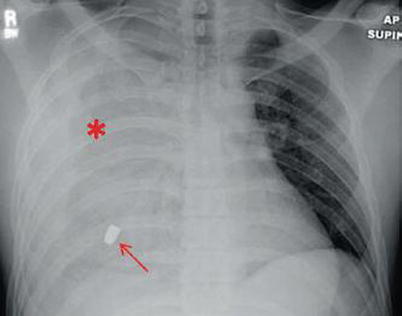

Fig. 15.5

Large right hemothorax (red asterisk) after penetrating trauma (red arrow)

Hemothorax is another common pleural abnormality after penetrating trauma. The source of bleeding may be from the chest wall, intercostal arteries, internal mammary arteries, lung parenchyma, heart, or mediastinal vessels. Typically, a volume of 200–300 mL is necessary to be picked up on conventional chest x-ray. These radiographic findings are due to radiodense blood collecting in the pleural space. Presentation may vary from an opacified hemothorax (Fig. 15.5) to a subtle blunting of the involved costophrenic recess. Because blood serves as an excellent culture medium for bacteria, drainage is important for significant collections. Often after tube thoracostomy, “follow-up” chest x-rays are obtained daily to judge adequacy of drainage. We caution against this practice as they are often misleading in determining the amount of residual blood in the thoracic cavity. Computerized tomography is much more accurate in evaluating which patients will require further evacuation and has been proven in a prospective trial.